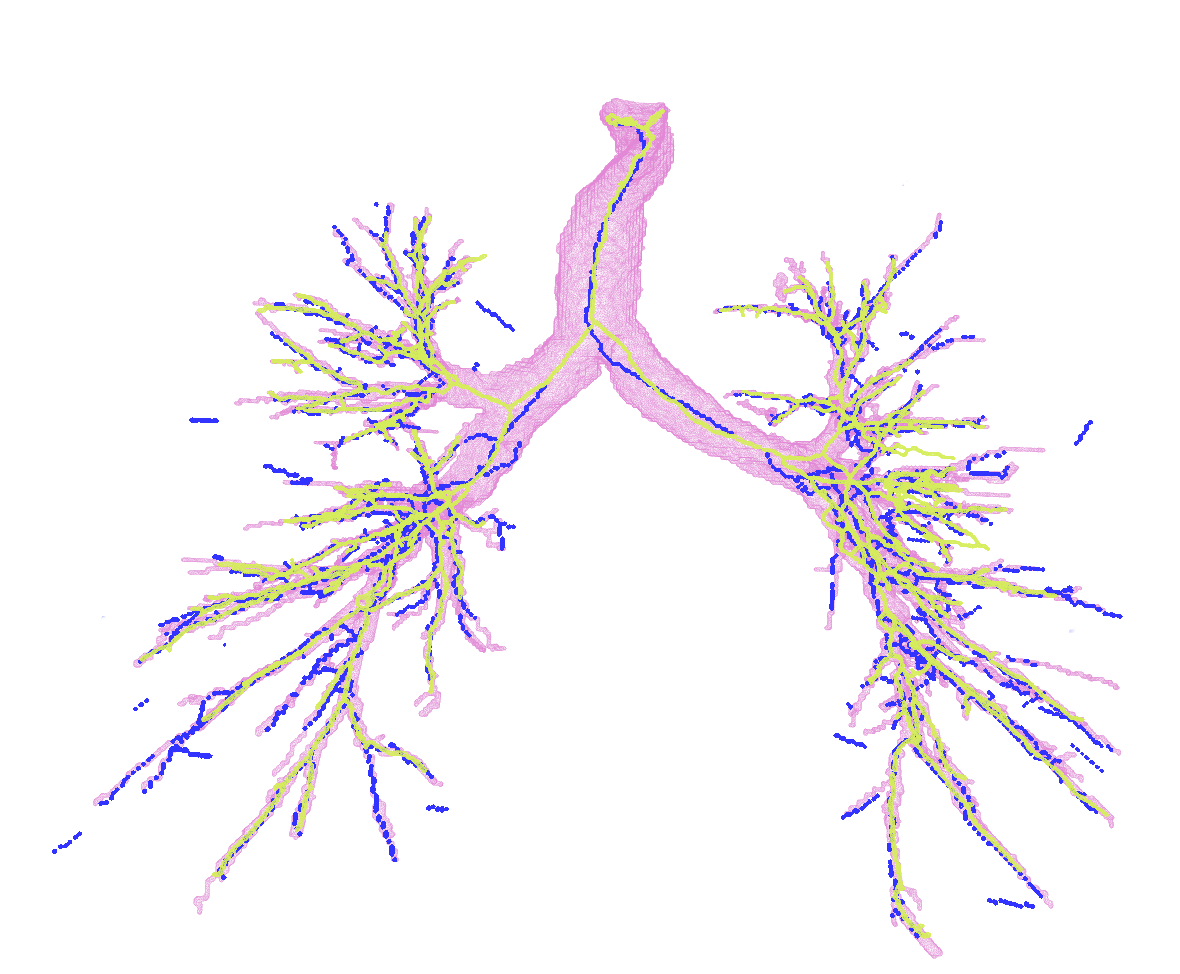

In Figure 2, first we present the predicted subgraph for one of the images. The gray dots are nodes of the over-complete graph with features, , extracted using Bayesian smoothing; the edges are colour-coded providing an insight into the performance of the method: yellow edges are true positives, red edges are false positives and blue edges are false negatives compared to the ground truth connectivity derived from the reference segmentations. Several of the false negatives are spaced closely, and in fact, do not contribute to the false negative error, , after generating the binary segmentations. The figure to the right in Figure 2 shows four predicted centerlines overlaid with the reference segmentation and centerlines from the voxel-classifier approach. Clearly, the MFN method is able to detect more branches as seen in most of the branch ends, which is also captured as the reduction in in Table 1. Some of the false positive predictions from MFN method appear to be a missing branch in the reference as seen in the first of the four scans. However, there are few other false positive predictions that could be due to the model using only pairwise potentials; this can be alleviated either by using higher order neighbourhood information or with basic post-processing. The centerlines extracted from MFN are slightly offset from the center of airways at larger scales; this could be due to the sparsity of the nodes at those scales and can be overcome by increasing resolution of the input graph.